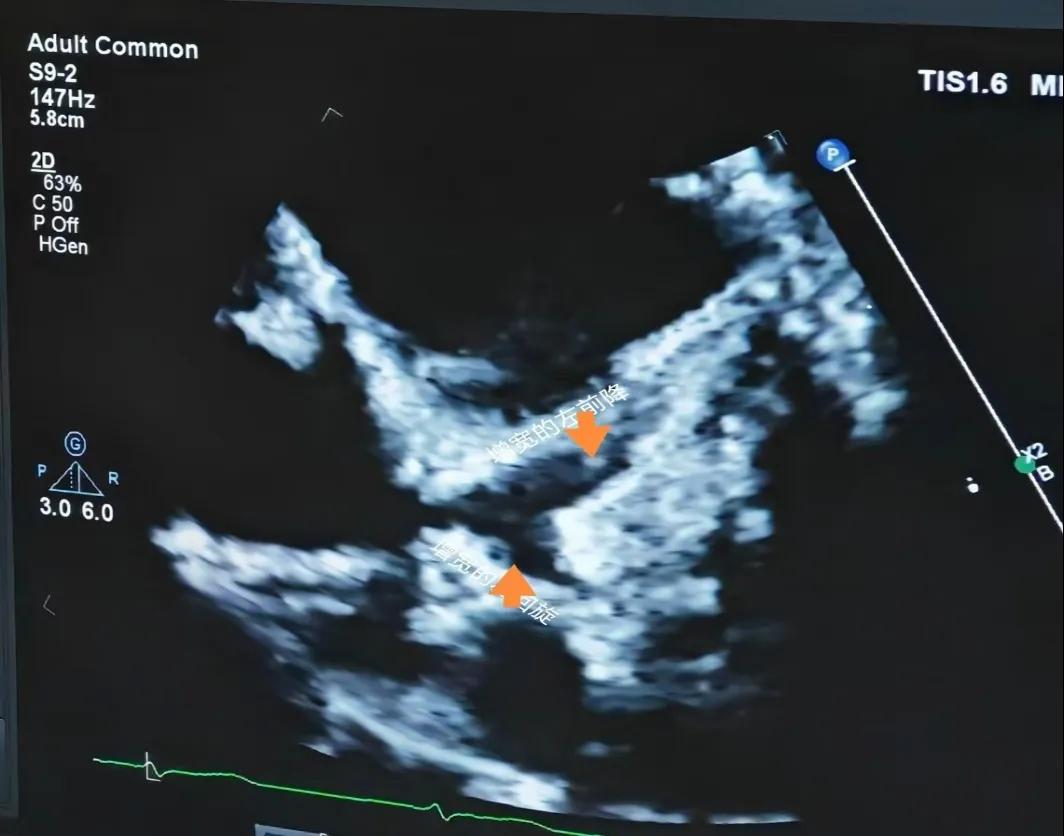

(川崎病患兒:增寬的右側(cè)冠狀動脈)

(川崎病患兒:增寬的左前降支和左回旋支)